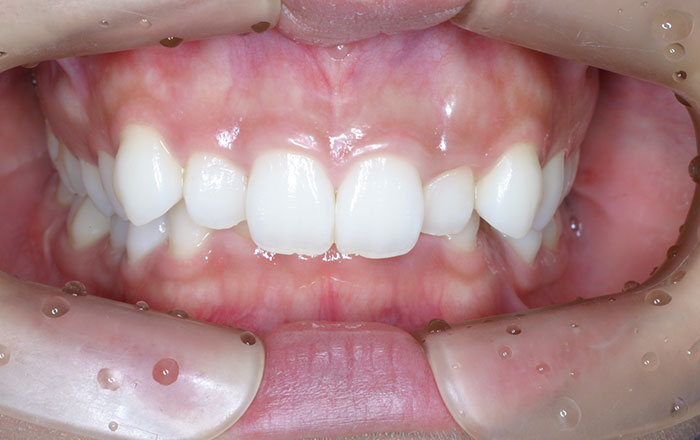

①矯正で理想の噛み合わせに近づける

歯列矯正を行って、理想の噛み合わせに近づけることで、歯や顎の不快さなどの軽減が期待できます。

噛み合わせが良くない状態で強く噛んでしまう部位がある場合は、歯全体で噛めるように治療していきます。

※矯正は、歯ぎしり・食いしばりを完全になくすものではありません。